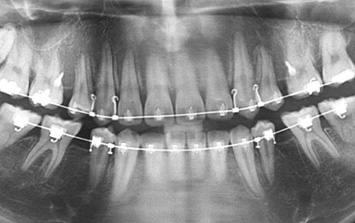

26세 여환으로 우측 아래 어금니 매복으로 다른 치과에서는 어금니 2개를 모두 발치 해야 한다는 진단을 받고 내원.

환자분이 매복된 치아를 꼭 살리고 싶다고 하여 사랑니는 발치를 하고 매복되어 있는 치아는 교정으로 견인 하기로 함.

구강외과 협진으로 안정적으로 사랑니를 발치하고 치아교정을 진행하였습니다.

어금니와 사랑니가 수평 매복되어 있는 상황

사랑니 발치 후 매복된 치아 견인

교정 후 치조골 또한 온전하게 재생됨

구강외과 협진- 사랑니를 발치 한 이유는 매복치아를 발치 할 경우 다량의 뼈를 제거해야 하고

그로 인하여 아래턱뼈가 약해질 가능성이 있다고 판단했기 때문입니다.